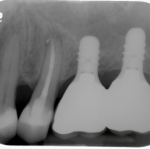

The bone used in a sinus lift may come from your own body (autogenous bone), from a cadaver (allogeneic bone) or from cow bone (xenograft). You will need X-rays taken before your sinus lift so the dentist can study the anatomy of your jaw and sinus. You also may need a special type of computed tomography (CBCT) scan. This scan will allow the dentist to accurately measure the height and width of your existing bone and to evaluate the health of your sinus.

In the most common sinus augmentation procedure, a small incision is made on the premolar or molar region to expose the jaw bone. A small opening is cut into the bone, and the membrane lining the sinus is pushed upward. The underlying space is filled with bone grafting material, either from your own body or from a cadaver. Sometimes, synthetic materials that can imitate bone formation are used. After the bone is implanted, the incision is stitched up and the healing process begins.

After several months of healing, the bone becomes part of the patient’s jaw and dental implants can be inserted and stabilized in this new sinus bone.